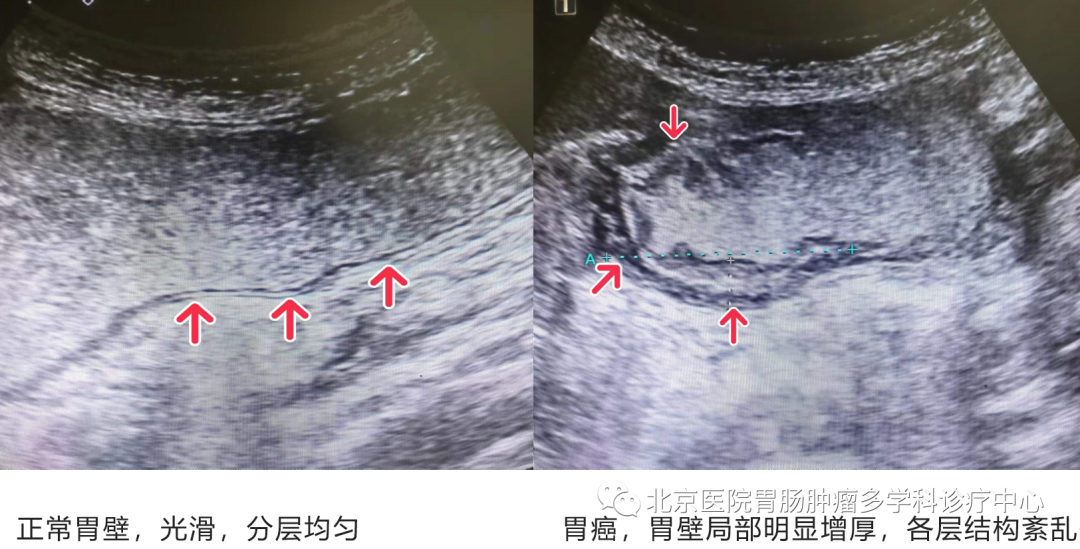

胃超声检查可观察胃黏膜各层次结构如黏膜层、肌层、浆膜层,可对病变的位置、大小、浸润程度、转移情况进行全面评估,皮革胃、胃间质瘤、胃淋巴瘤等有些粘膜外肿瘤胃镜检查有一定局限,胃超声检查可以很好的辨别。胃超声检查是动态观察,可实时反复观察胃肠蠕动,对于胃肠功能性问题,如胃食管反流、胃十二指肠反流等有临床提示意义。胃充盈造影剂后检查还可以清晰地显示胃周邻近器官如胰腺、后腹膜淋巴结等病变情况。可作为胃肠道炎症、溃疡、恶性肿瘤等内科药物治疗疗效追踪监测的⽅法之⼀,也可作为健康人群的筛查方法。在2018年国家医政医管局出版的《胃癌诊疗规范》中列为胃癌患者的常规检查,是卫健委专家推荐的胃肠道肿瘤早诊防查适宜技术,可以早期发现胃肠道炎症性病变及早期肿瘤、进展期胃肠癌,可判断病变的浸润情况,是胃肠癌T分期的有益补充